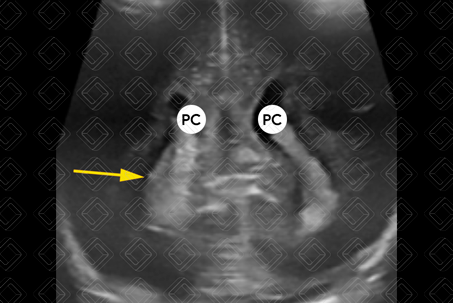

Descrição das figuras 3, 4 e 5: Ultrassonografia transfontanela; imagens coronais e parassagital direita. Área ecogênica visualizada no interior do corno frontal do ventrículo lateral direito (seta vermelha), estendendo-se no corte parassagital direito no interior do ventrículo lateral deste lado (estrela), deixando o plexo coroide (PC) deste lado mais “gordinho” e irregular em comparação ao esquerdo (seta amarela), compatível com hemorragia de matriz germinal grau II à direita. Nesse caso, não há dilatação do sistema ventricular.

• Grau II: H emorragia estendendo-se para o sistema ventricular, notadamente o plexo coroide, sem causar dilatação do sistema ventricular (figuras 3, 4 e 5);